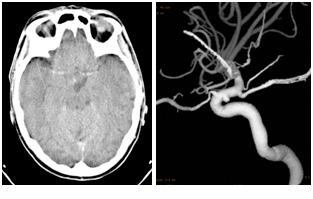

This 40-year old normotensive woman had sudden headache before landing of an intercontinental flight from Egypt to Italy which worsened in the shuttle of the airport.

On admission at our Hospital, CT scan demonstrated a focal SAH in the right pericarotid and sylvian cisterns and cerebral angiography showed a small “blister” aneurysm of the infero-medial portion of the right supraclinoid ICA (Figure 2). A right pterional craniotomy with anterior clinoidectomy was performed. A non saccular carotid aneurysm was found: clipping was not possible and wrapping of the arterial dilatation was performed. The exploration of the ICA and its branches did not reveal any changes. Postoperative course was uneventful. At postoperative control angiogram at two weeks the aneurysm was unchanged and stenosis of the right anterior cerebral and posterior communicating arteries due to vasospasm or dissection was present (Figure 3). At one year, the patients remained well and the narrowing was unchanged, confirming the hypothesis of a residual dissection.

Figure 2 Case 2: CT-scan shows a SAH in sylvian fissure and right pericarotid cistern (left); carotid angiogram reveals a small “blister” aneurysm of the infero-medial portion of the right supraclinoid ICA (right).